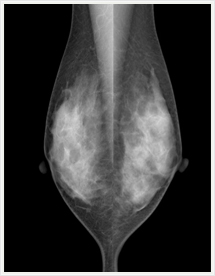

画像紹介

画像は左右を比較するように表示され、気になるところは、拡大して見ることができます。